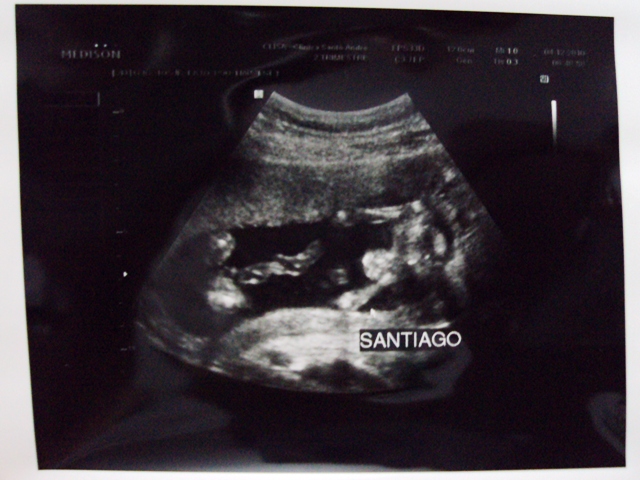

Hoje, enfim, Jôse fez o terceiro exame ultrassom e deu para ver o sexo do bebê. Segundo Dr. Pablo, é um Menino!

O mais novo integrante da família deverá se chamar Jorge Santiago.

O sacaninha está deitado sob o seu lado esquerdo e de frente pra o mundo. Está observando tudo. Ai em cima na foto do ultrassom, logo acima do nome é o rosto. Do lado esquerdo, está as perninhas encolhidas. Não se assustem! isso ai tudo é o cordão umbilical. Dizendo Dr. Pablo, que no meio das pernas tem um pinto e o saco escrotal. É mais um menino!